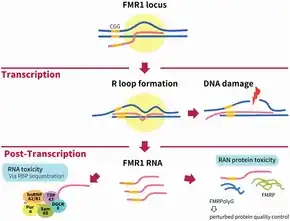

FMR1 mRNA is found to be elevated in patients with FXTAS[9] in contrast to FXS, where the FMR1 gene is transcriptionally silenced via DNA methylation.[10] In both diseases the FMR1 gene product, Fragile X mental retardation protein (FMRP) is diminished, but in FXTAS this is believed to be mediated by RNA toxicity, while in FXS, FMRP is absent due to transcriptional silencing.[9]

The etiology of Fragile X-associated tremor/ataxia syndrome, has a mutation known as a CGG triplet repeat, which occurs within the FMR1 gene[11]